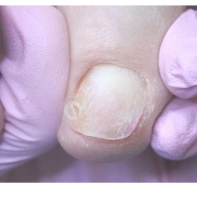

Вросший ноготь (онихокриптоз) — распространенная патология, вызванная изменением направления роста ногтевой пластины. Ногтевая пластина с измененной траекторией роста начинает упираться в боковой валик, а в дальнейшем прорезает мягкие ткани валика, вызывая воспаление и гнойный процесс. Онихокриптоз может возникнуть на любом пальце ноги или руки, но чаще всего поражает большие пальцы стоп.

- Первая характеризуется отечностью, покраснением и пульсирующей болью в той части околоногтевого валика, куда врастает ногтевая пластина.

- При второй ноготь уплотняется, приобретает тусклый цвет. В месте, где происходит травматизация мягких тканей пальца, возникает небольшая язвочка, при надавливании на которую может выделяться гной.

- При третьей стадии ногтевая пластина становится тонкой и ломкой. Околоногтевой валик увеличивается в размерах, в области вросшего ногтя разрастается грануляционная ткань — богатая сосудами и новыми клетками молодая соединительная ткань зернистой структуры.